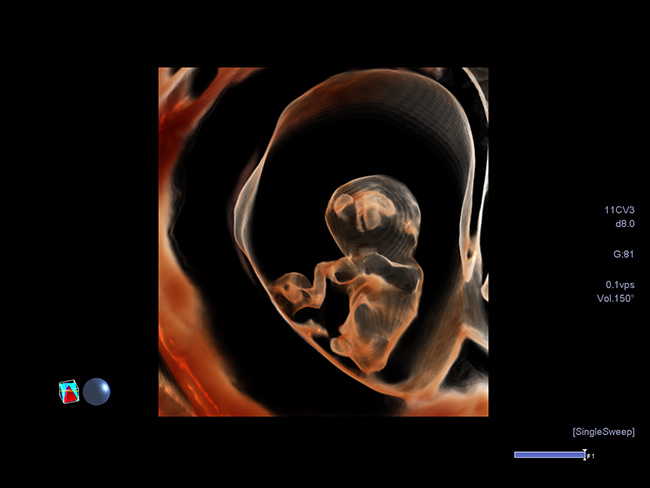

Якісна об'ємна візуалізація з високою роздільною здатністю може допомогти оцінити вагітність вже на перших етапах життя. В цьому прикладі - дихоріонічна вагітність з двійнятами на 9 тижні, де чітко визначена перегородка між обома мішками.

Режим Luminance забезпечує тривимірну реконструкцію одержуваних даних в природному вигляді з високою якістю і роздільною здатністю для максимально реалістичної візуалізації плода вже в першому триместрі.